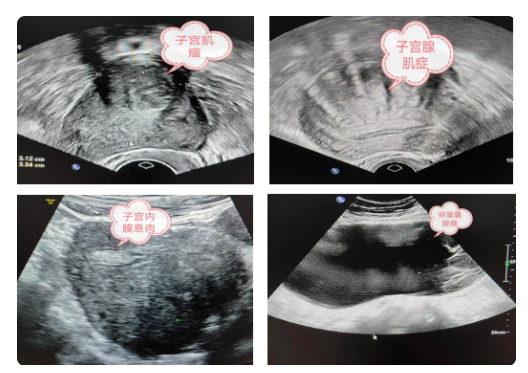

如上圖所示,盆腔彩超檢查的內(nèi)容是宮頸外口以內(nèi)的部分:包括子宮、卵巢、附件,常見的疾病如子宮肌瘤,子宮腺肌癥,子宮內(nèi)膜息肉,卵巢腫瘤,輸卵管積水、積膿、盆腔包塊等。(部分常見疾病超聲表現(xiàn)如下圖:)